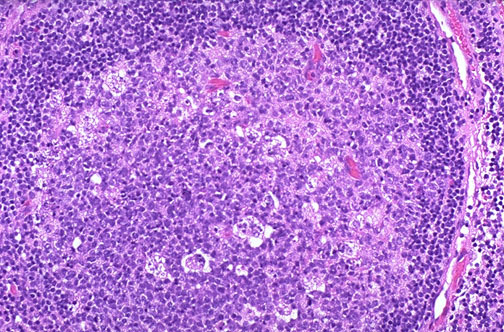

This is a more pronounced reactive change in a lymph node, with a larger follicle and germinal center containing ‘tingible body’ macrophages. These large macrophages are involved in phagocytosis of antigenic material passed from follicular dendritic cells to be processed into peptides. In general, lymph nodes in a benign reactive process are more likely to enlarge quickly and become tender.